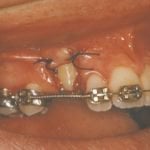

In cases where the eyeteeth will not erupt spontaneously, the orthodontist and oral surgeon will work together to get these teeth to erupt. Each case must be evaluated on an individual basis, but treatment will usually involve a combined effort between the orthodontist and the oral surgeon. The oral surgeon will expose and bracket the impacted eyetooth.

The goal is to erupt the impacted tooth and not to extract it. Once the tooth has moved into its final position, the gum around it will be evaluated. In some circumstances, there may be some minor “gum surgery” required.

Exposure and Bracketing of an Impacted Cuspid

What to expect from surgery to expose & bracket an impacted tooth

The surgery to expose and bracket an impacted tooth is a very straightforward surgical procedure that is performed in the oral surgeon’s office. For most patients, it is performed using laughing gas and local anesthesia. In selected cases it will be performed under IV sedation if the patient desires to be asleep, but this is generally not necessary for this procedure. If the procedure only requires exposing the tooth with no bracketing, the time required will be shortened by about one half. These issues will be discussed in detail at your preoperative consultation with your doctor.